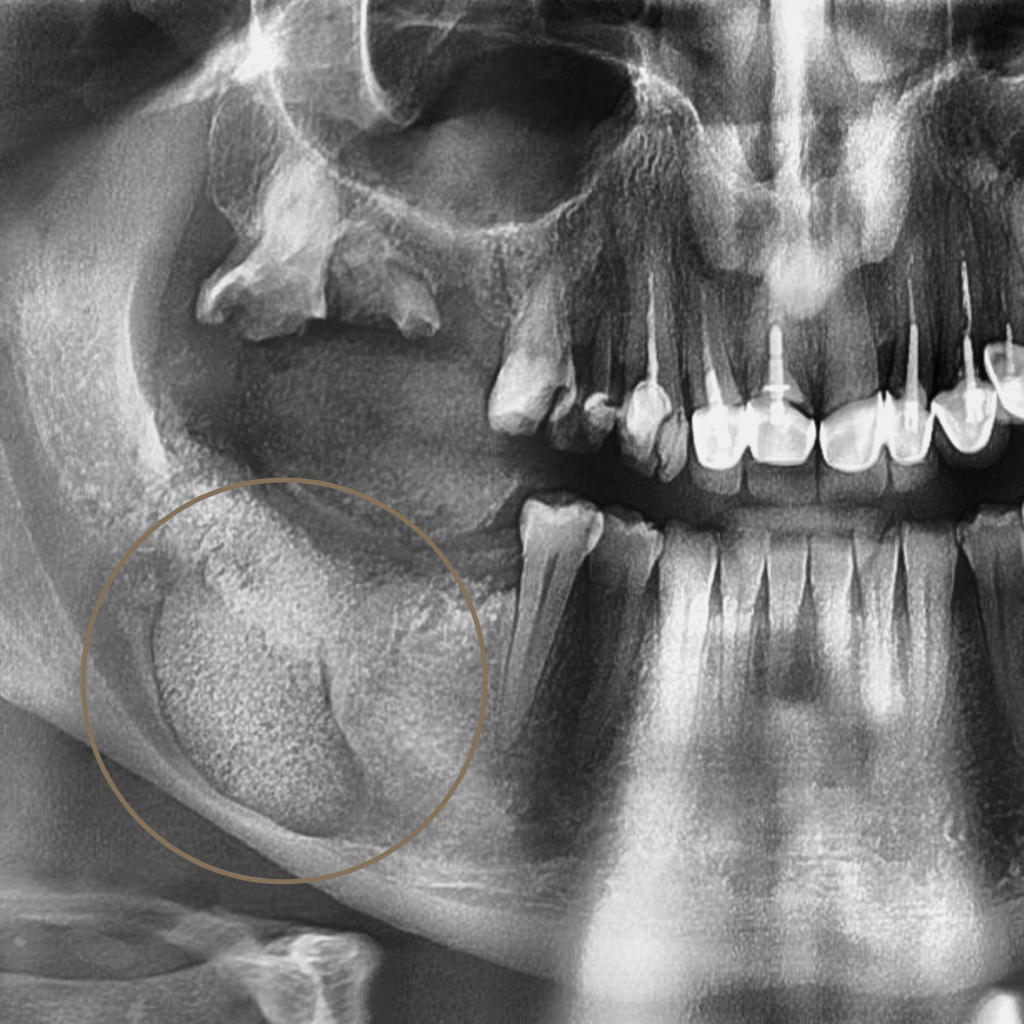

Промени в костта или меките тъкани на лицево-челюстната област изискват прецизна диагностика и ясен терапевтичен план. Навременното установяване на характера на лезията е ключово за правилното лечение и прогнозата.

В лицево-челюстната област туморите и кистите могат да засегнат костните структури, венците, езика, бузите и други тъкани на устната кухина. В клиничната практика се срещат както доброкачествени образувания, така и предтуморни или злокачествени състояния, които изискват навременна и точна диагностика.

Извършва се клиничен преглед и анализ на образните изследвания, за да се оцени локализацията, обемът и характерът на формацията.

Възстановяване и проследяване

След лечението се провеждат регулярни контролни прегледи и образно проследяване. При необходимост се планират последващи възстановителни процедури, като костна регенерация, имплантология или протетика.